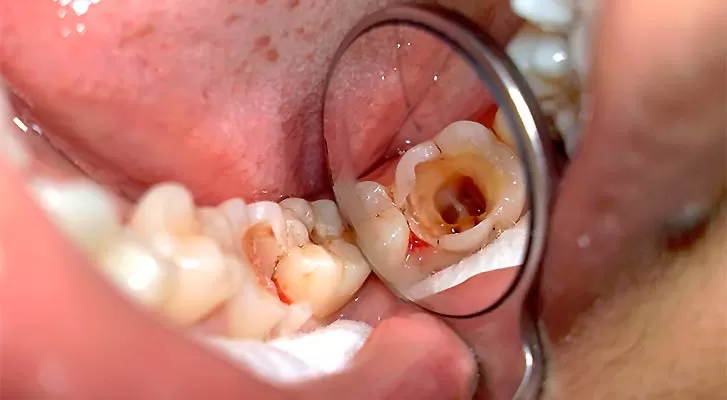

ПУЛЬПИТ

Помогите убрать боль от пульпита . я его маму ебал.

полтора года назад был на одном зубе . вроде 1 ночь ирония судьбы как болел . и весь потом еще ночь и потом еще смену на работе. вообщем 3 дня будто. пил ибупрофен и кето(все хуйня не работает )я точно помню узнал про дексонал на конец 3его дня выпил и всё боль прошла и забил леденец . найдя волшебную таблетку понял что если опять будет болдеть или на другом зубе просто выпью таблетку и похуй.

опкаывазется у меня щас сгнил 2ой зуб и К МОЕМУ БЛЯДСКОМУ УДИВЛННИЮ ВОЛБШЕБНАЯ ТАБЛЕТКА НЕ РАБОТАЕТ .этот блядский нерв не успаккаиватся. ед что помогает пить холодную воду (просто держать эту воду над зубом) и пару минут норм .

У тебя болит и не проходит, потому что бактерии всё ещё живут в дырке и едят плоть твоего зуба не давая мягкой ткани загрубеть и зажить.

Твоя задача вычистить бактерии из дырки, а оставшиеся убить нахуй.

1. Идёшь в аптеку и покупаешь такой комплект. Смотри обязательно чтобы жижа для полоскания была обеззараживающая, самая мощная, желательно с хлоргекседином.

2. Ёршиками пытаешься вычистить всё вокруг больного зуба

3. Смачиваешь ёршики в жиже

4. Спринцовкой тёплой водой пол часа вымываешь всё из дырки. Прям напором стараешься в дырку попасть.

5. Потом пару раз загоняешь в эту дырку жыжу

6. И потом ещё минут 20 просто полощешь жыжой кбиваешь все микробы в полости рта

7. Через пол часа боль отступит, и зуб начнёт заживать, ткань грубеть.

Повторяй такое каждые 3 - 4 дня,и даже больной зуб не будет тебя тревожить.